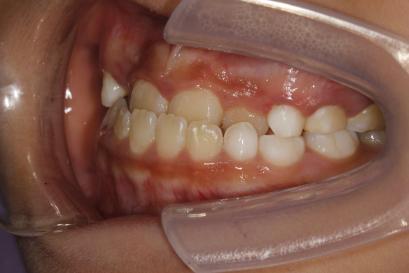

案例三:

治疗前

治疗后